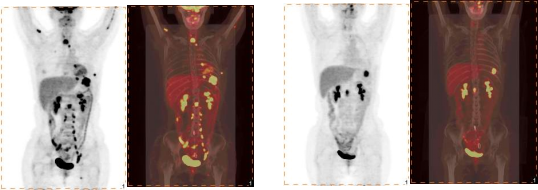

PET-CT并不是二者功能的简单叠加,二者优势互补,达到1+1>2的效果。PET可以显示病灶病理生理特征,更容易发现病灶。CT可以精确定位病灶,显示病灶结构变化,达到同时反映病灶的病理生理变化及形态结构的目的,给出最具个体化治疗的参考方案,提高了疾病诊断的准确性、治疗方案的合理性。PET-CT是目前最先进的分子影像检查仪器,是“筛查肿瘤的神器”,被业界喻为探测肿瘤的“雷达”、发现肿瘤的“神探”。

肺癌评估疗效和监测复发:女性,42岁。因左肺癌治疗后PET/CT发现多发转移。经过头部伽马刀治疗、化疗4个疗程、胸部放疗后,半年后PET/CT随访,颈部和腹膜后多数病灶消失或缩小。左侧背侧增厚胸膜、L1椎体水平腹膜后淋巴结FDG代谢仍异常增高,提示肿瘤放化疗后部分缓解(PR)。